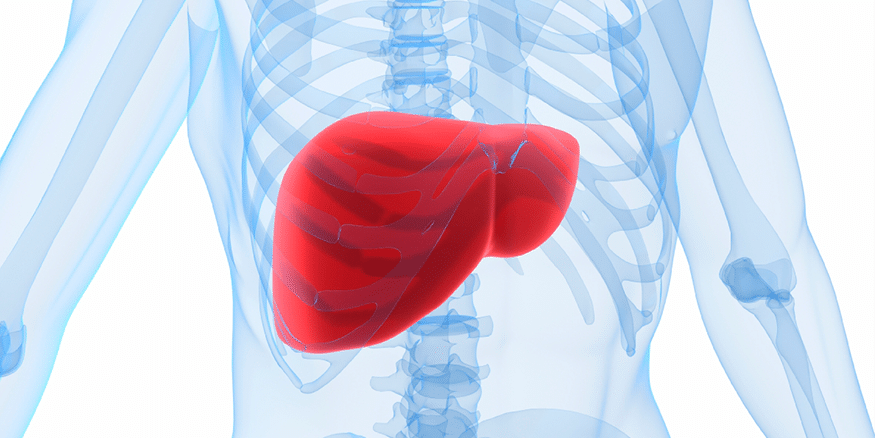

Liver

Right liver lobe

orange highlight

Left liver lobe

yellow highlight

Falciform ligament

Coronary ligament

Round ligament

Caudate lobe

blue highlight

Quadrate lobe

green highlight

Porta hepatis

What do all these make up (this is the posterior liver)

Inferior vena cava

Hepatic artery

Hepatic portal vein